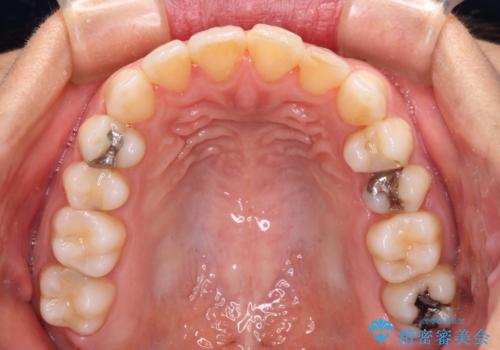

前歯の叢生をいつの間にか改善 インビザラインによる矯正治療

- 前歯のデコボコを気にして来院された患者様です。

IPR(歯と歯の間を削る)によってデコボコが解消するように設計し、インビザラインにより治療を行うこととしました。

下顎善の叢生をもう少し改善したかったのですが、患者様は十分に整ったとのことで治療を終えることになりました。